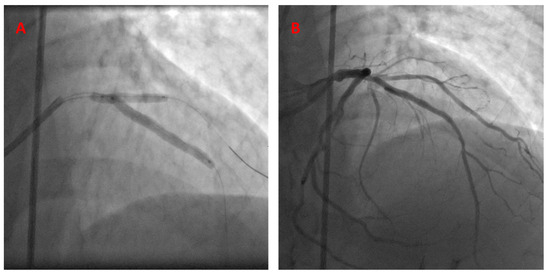

- Case # 3

| Case 3 | 41 yo | LAD/D1 | LAD stent, D1 balloon | 11 years | 11 y, NR |

| Case 3 | LAD ISR | D1 is patent |